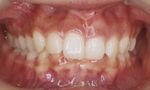

大人の矯正治療 (第二期治療)

永久歯の矯正治療(12歳以降から)

マルチブラケット装置による治療です。(一本ごとの歯にブラケットを装着し、ワイヤーを通して歯並びを治します。)

治療期間は、個人差もありますが1年半~3年が目安です。その後、ワイヤーで治した歯並びを維持するための保定装置での観察を2年ほど行います。